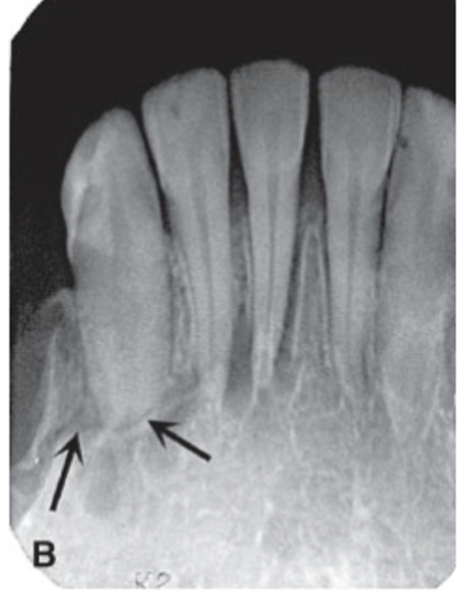

root fracture

radiolucent line travels through root of tooth — horizontal, vertical, or oblique

widening of PDL space indicates presence of fracture

vertical root fracture has vertical separation of apical third of root

shows radiolucent area